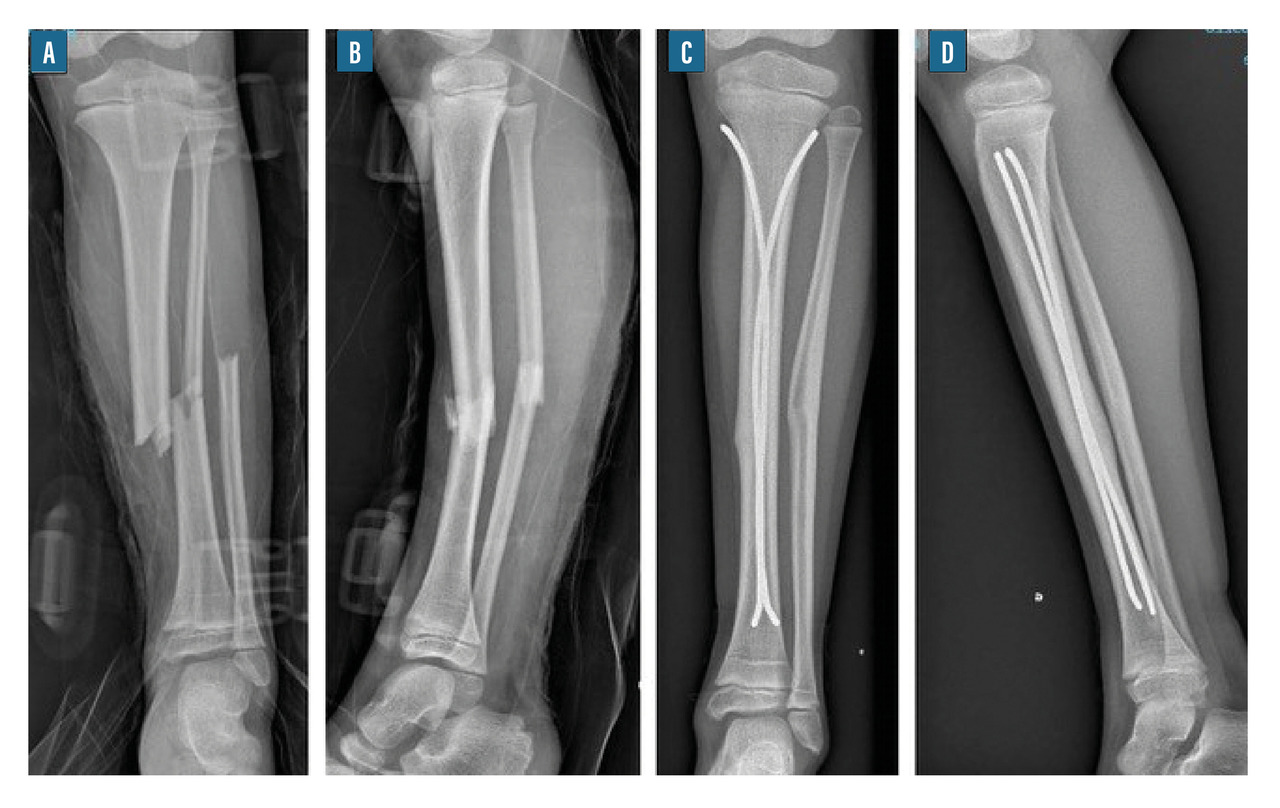

• l’embrochage centromédullaire élastique stable (ECMES) est une méthode couramment utilisée en traumatologie infantile. Elle consiste à mettre des broches cintrées et béquillées dans le canal médullaire et obtenir ainsi une stabilité élastique du foyer (fig. 10). Toute force appliquée sur l’os provoque un déplacement avec retour élastique à l’état d’équilibre qui est l’état anatomique ;12

Les fractures diaphysaires du fémur sont très fréquentes et de bon pronostic. Elles se voient à tout âge, mais surtout chez l’enfant jeune. Le traitement est très différent selon l’âge de l’enfant. Lorsque l’enfant est jeune, le plâtre pelvipédieux est le traitement de référence. Lorsque l’enfant est plus grand, au-delà de 6 à 8 ans, la technique d’embrochage centromédullaire élastique stable est la méthode de choix. Lorsque l’enfant est plus grand encore, il est possible de discuter la mise en place d’une fixation interne par clou centromédullaire. Les complications des fractures du fémur sont le raccourcissement et les cals vicieux.